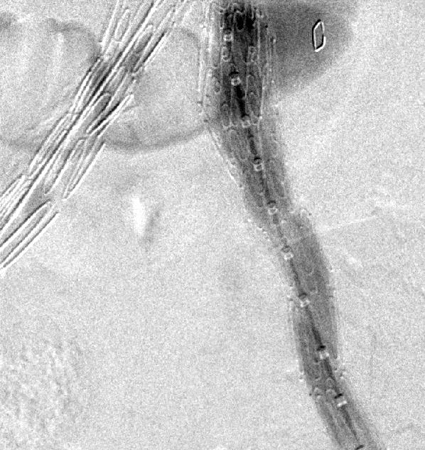

Extension stent graft deployed for the same type I endoleak (encircled)

University of Michigan, specifically the cases of Dr Upchurch reflecting the Departments of Vascular Surgery and Radiology